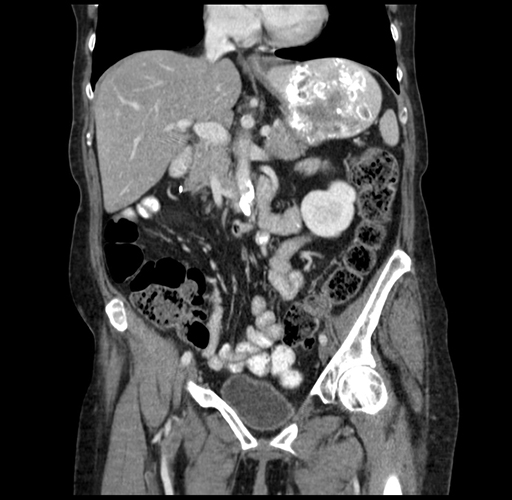

Pre-Chemo: Coronal Venous